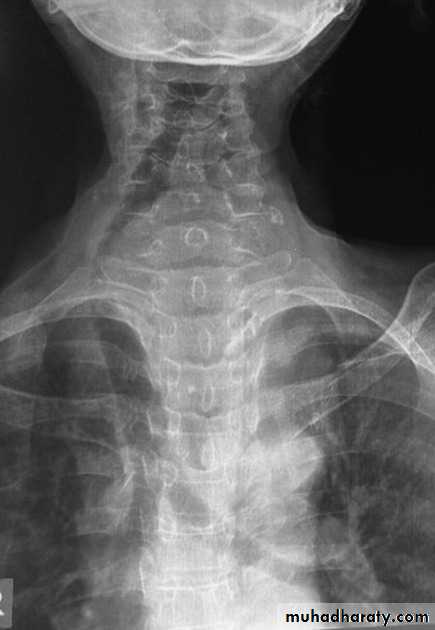

22.Retrophyrengeal abscess